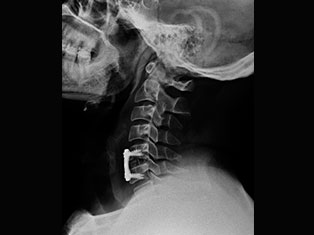

Degenerative Spine

The phrase "degenerative changes" in the spine refers to osteoarthritis of the spine. Osteoarthritis is the most common form of arthritis. Doctors may also refer to it as degenerative arthritis or degenerative joint disease.